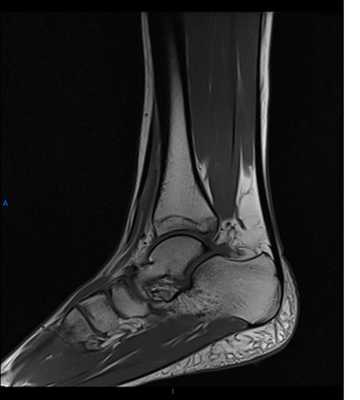

Пример повреждения связок голеностопа. Травма передней межберцовой связки

На МРТ голеностопного сустава определяется частичный или полный разрыв связки. На рентгенограммах голеностопного сустава при 1-2 степени повреждения связок изменения отсутствуют, при 3 степени иногда просматривается небольшой фрагмент костной ткани, оторвавшийся от кости в области прикрепления связки.